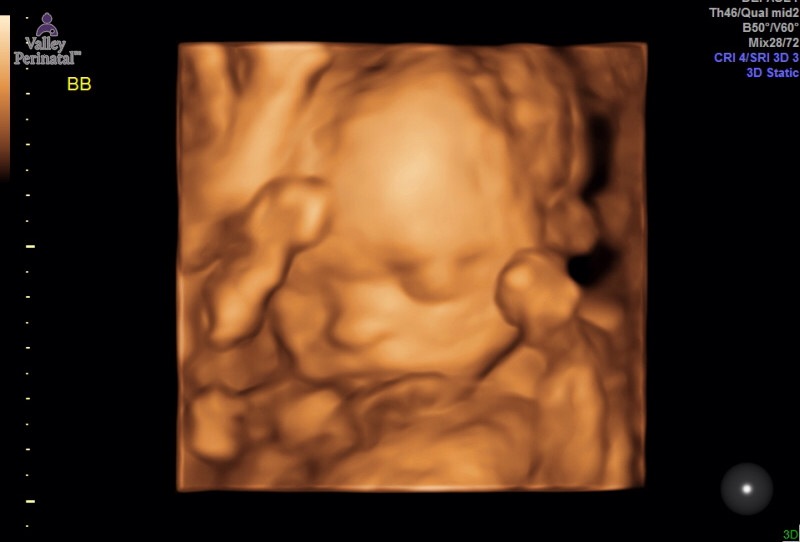

Here’s the two best pictures from the ultrasound. Of course baby B would not sit still so his picture is a little blurry but I promise you he is perfection! Luke thinks baby A looks like a Prudence while baby B looks like a Leonard and I’m just relieved they look like babies!!

After I was done being violated, while my husband watched no less, we got to see the boys! And OMF-ingG they look completely different at 22.5 weeks than they did at 19.5. Not gonna lie, at 19.5 weeks they were a little creepy looking – all skin and bones, no chubby cheeks or distinguishing features. Now they look like little boys with fat cheeks and little button noses. I may actually have a couple little chunkers on my hands as they both measured almost a week ahead in their growth and weight! I love fat babies. Like there is nothing cuter than a baby who’s fat rolls spill over themselves but I would prefer to not have to birth fat babies – you know just get healthy while you’re in me and then blossom into the cutest chunk ever  when you get to the outside world, be nice to your mom’s insides please!